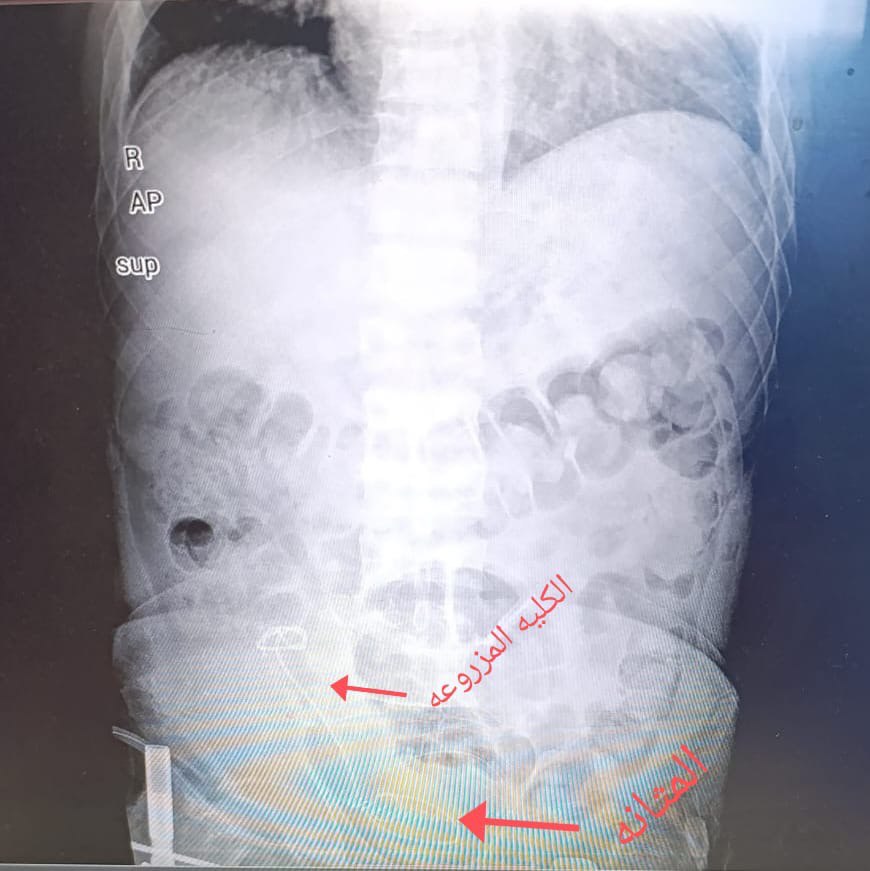

وكان المريض يعاني من فشل كلوي سابق، وقد خضع لعملية زراعة كلية خارج البلاد العام الماضي، قبل أن يراجع المستشفى وهو يشكو من انسداد في حالب الكلية المزروعة، ترافق مع توسّع في الكلية وارتفاع ملحوظ في وظائفها، الأمر الذي شكّل تهديدًا حقيقيًا بفقدان الكلية المزروعة والعودة إلى الغسيل الكلوي مجددًا.

ورغم تعقيد الحالة الصحية للمريض، ولا سيما مع إصابته بارتفاع شديد في ضغط الدم والتهاب الكبد الفيروسي من النوع (C)، فإن ذلك لم يكن عائقًا أمام الكوادر الطبية والتمريضية في المستشفى، التي بادرت إلى إجراء عملية ناظورية وجراحية دقيقة ومعقدة لفتح حالب الكلية المزروعة، مع وضع قسطرة حالبية لضمان استمرارية انسيابية جريان البول من الكلية إلى المثانة، وتأمين شفاء آمن للحالب.

وقد تكللت العملية بالنجاح، حيث عادت الكلية إلى حجمها الطبيعي، وتحسنت وظائفها لتصل إلى المستويات الطبيعية، ليغادر المريض المستشفى لاحقًا وهو يتمتع بصحة جيدة وعافية تامة.